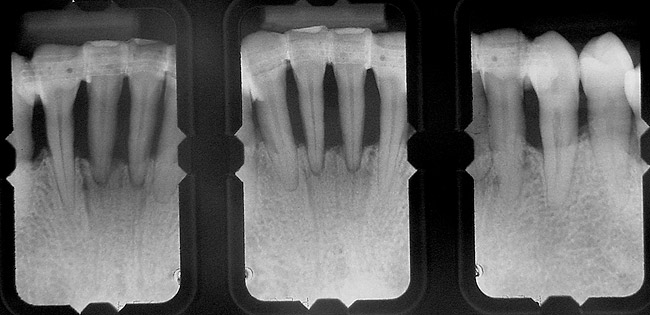

When fiber-reinforcing materials were introduced, the focus for their use was for periodontal splinting and stabilization resulting from tooth mobility.6,10,16,41-43 There is no doubt that splinting does reduce tooth mobility while the splint is in place.44 In the last decade, research supports the use of periodontal splinting as recommended therapy to stabilize those teeth to improve long-term prognosis.45-47 In a long-term clinical evaluation of splinting over a period of 48 to 96 months, using the original Ribbond Reinforcement Ribbon in fiber-reinforced composite resins was highly successful.17 The success of these splints can be attributed to close adaptation of the fiber ribbon to the tooth surface combined with cross stabilization of the mobile teeth by placing adhesive composite resin on the facial surfaces (Figure 4A, Figure 4B, Figure 4C, Figure 4D, Figure 4E).34,35 Splinting of traumatized teeth with fiber-reinforcing materials and adhesive composite resin has also been reported.48,49 When using fiber to stabilize the traumatized tooth or teeth or for tooth stabilization after re-implantation, the tooth must be allowed to have some movement and not be fixed in place.50,51

In vitro studies have demonstrated that the use of unidirectional glass-fiber reinforcement in the connector areas of FPDs contributes to significant composite reinforcement.29,36-38,66-68 Similar findings have been reported with a leno-weave UHMWPE and triaxial weave UHMWPE fiber.20,33,36 Fiber-reinforcing materials used by a dental laboratory are either resin pre-impregnated glass fibers, pre-polymerized composite resin surrounding glass fibers, biaxial braid UHMWPE, leno-weave UHMWPE, or a triaxial weave UHMWPE (Table 3). Typically, the preparation designs for the abutment teeth are inlay or onlay preparations (Figure 6A, Figure 6B, Figure 6C, Figure 6D). They are highly successful and can provide the patient with clinical service for more than 5 to 10 years.69 These restorations must be cemented using an adhesive resin technique with resin cements. Both etch-and-rinse adhesives with a self-cure or dual-cure composite resin cement or with a self-adhesive resin cement are indicated for cementing these restorations (Figure 7).36-38,70 Also, fiber-reinforcing materials are being used by dental laboratories in the fabrication of provisional restorations to reinforce and strengthen acrylic and composite-resin provisional materials.15,40,71